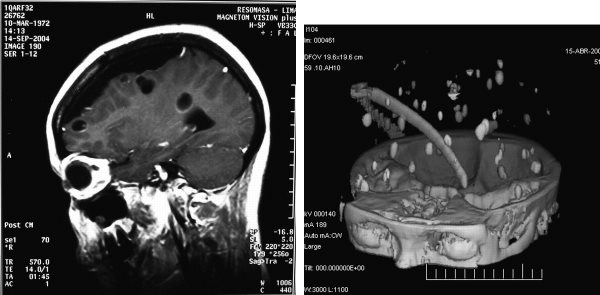

A 33-year-old Peruvian woman presented with a 10-year history of secondary generalized seizures. These images are from before and after treatment.

What is the disease and what was the treatment? What is the prognosis? Is there any continuing need for therapy?